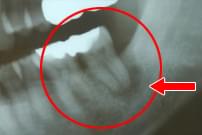

61歳 女性

右下7番に骨吸収が見られる。

GTR療法にて歯槽骨を再製。